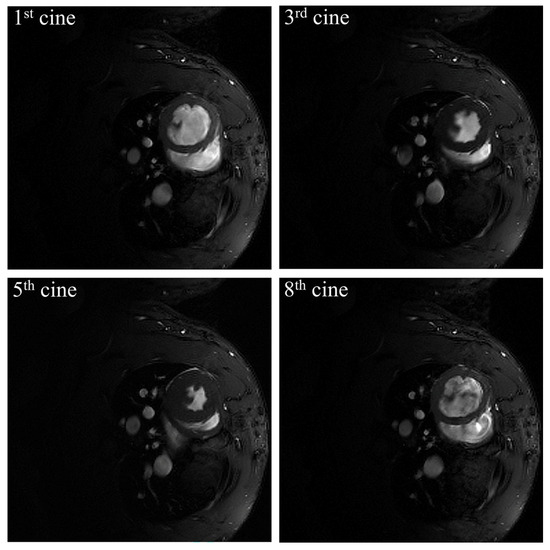

2.1. Cine MR Image of Rat Cardiac Data